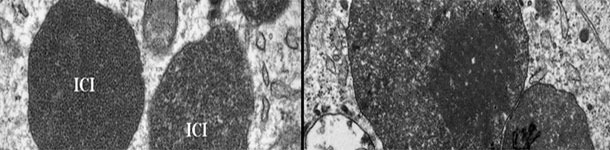

Le PCV2 est de plus en plus associé à des pathologies, dénominées collectivement maladies associées au PCV2 (PCVDs), comme MS-PCV2, MP-PCV2, ME-PCV2, MR-PCV2, IS-PCV2 et SDNP.